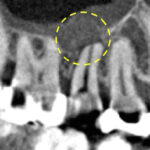

過去に根管治療を受けており、根の先に膿がたまり骨吸収が起こっている、根尖性歯周炎を発症している状態でした。ただ、根の先の病変の大きさはそこまで大きくはなく、現在の根管治療自体も不十分である点、虫歯による感染が疑われる点から、再根管治療により治癒する可能性は十分にある状態でした。

根管治療後12ヶ月のCT画像にて、はっきりと骨の回復・再生が認められました。患者様の「噛むと痛い」という症状も消失し、経過良好といえます。最終的には、ジルコニアクラウンを装着し、治療は終了となります。